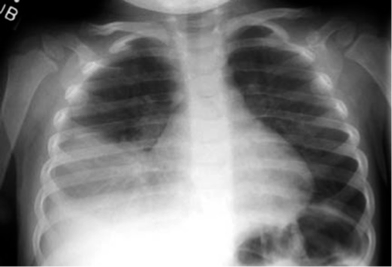

Tracheobronchial Tree Foreign Bodies

- Usually in infants and children

- Most FB’s are organic material (mostly food derivatives)

- Location: Mostly in the right side ( 60%)

Clinical Presentation

Choking, cough, gagging & cyanosis

Asymptomatic phase

Wheeze, intractable cough, persistent or recurrent chest infection

- due to emphysema, atelectasis, or infection

Treatment

To be initiated on clinical suspicion

- Bronchoscopy: in most cases

- Bronchotomy

- Pulmonary resection